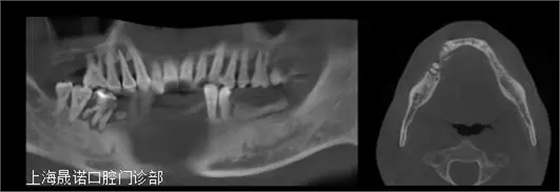

雙側(cè)后牙區(qū)唇側(cè)不規(guī)則骨缺損,最大骨寬度為7mm,高度尚可。CBCT掃描顯示下頜余留牙牙周支持組織重度喪失和伴根尖周病變、繼發(fā)齲。